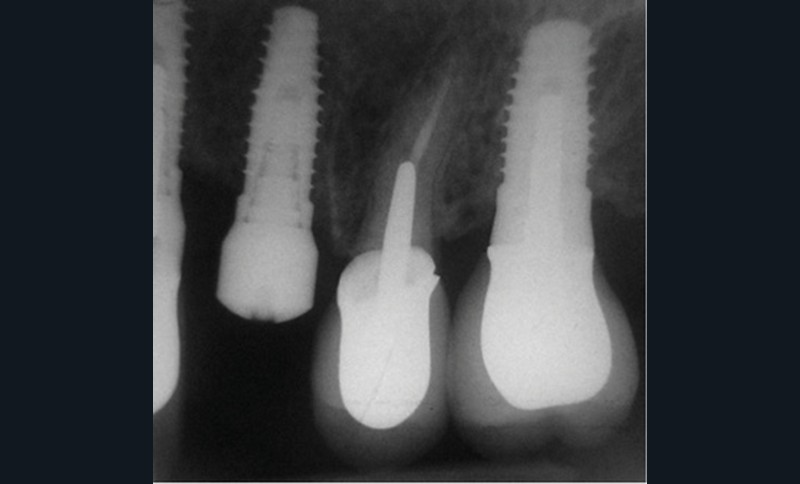

En mars 2016, la patiente se plaint d’une sensibilité sur la 25 et on note cliniquement une inflammation gingivale associée à un décalage apical du rebord marginal et de la ligne muco-gingivale en comparaison de leur situation visualisée au niveau des coiffes supra-implantaires. La couronne clinique est réduite et une infraposition avec une inocclusion d’environ 2 mm par rapport au plan d’occlusion et aux dents antagonistes est également notée (fig. 2 à 4). Un saignement au sondage ainsi qu’une poche de 5 mm en distal sont constatés. Le test de percussion est positif. Les tissus péri-implantaires adjacents ne présentent aucun signe de mucosite.

La radiographie péri-apicale au long cône confirme, sur la 25, un élargissement desmodontal, notamment en distal, des niveaux osseux mésio-distaux réduits par rapport aux clichés de contrôle précédents (les radiographies sont réalisées avec une technique parallèle avec des angulateurs de Rinn non personnalisés), un apex radiculaire normal et des niveaux osseux stables sur les implants adjacents (fig. 5). Le cisaillement systématique du fil dentaire lors de son passage confirme des points de contact très étroits entre 24, 25 et 26.